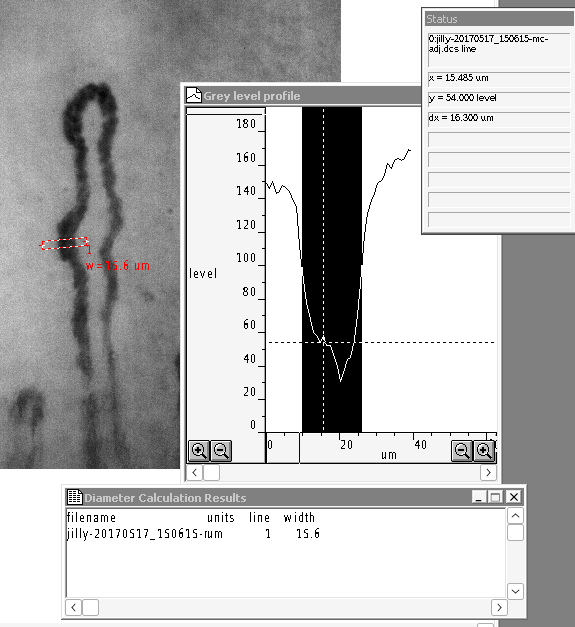

If one dimension line is activated, then Find Capillary Width will just measure using that dimension line. If no dimension line is active, then all dimension lines are calculated and the results listed in a Diameter Calculation Results window.

Single capillary line width measurement from active dimension line.¶

Capillary line width measurements of all dimension lines when no dimension line is active.¶

The width is measured from the greylevel profile. Better results can be achieved by increasing the line width to say 10 pixels. The greylevel is then averaged across the width of the measurement line.

Right click on the first node of the Dimension line to change its width. This width will also then become the new default line width.¶